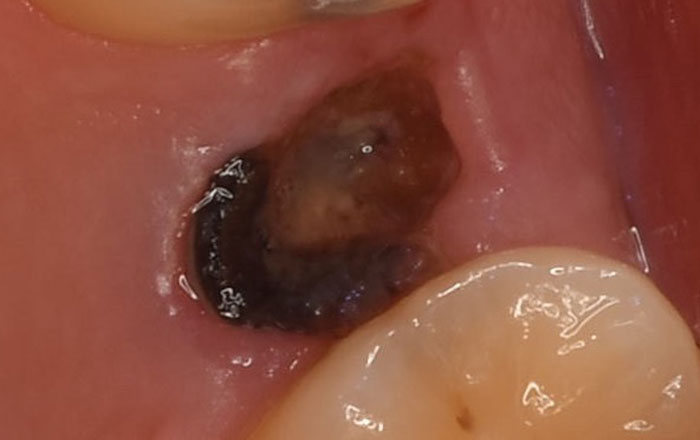

1)むし歯が原因の場合

むし歯は糖質(砂糖など)をエサにするバイ菌が酸を作り、お口の中が酸性になります。

酸性のままだと歯がどんどん溶けていき、やがて歯がボロボロに破壊されていきます。